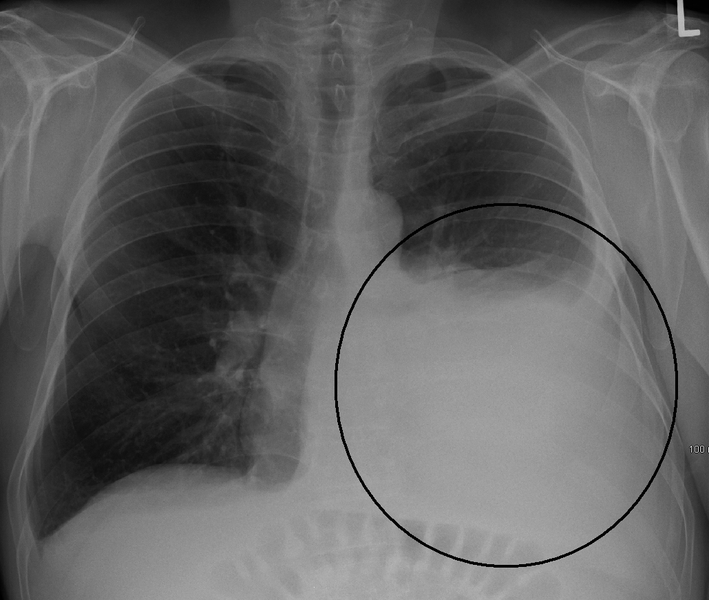

Cancer in the pleural cavity, malignant pleural effusion. Diseases and disorders malignant pleural effusion. Cancer that spreads into the pleural cavity, or the space between the lung and the chest wall, can create fluid or.

Pleural effusion wikipedia. In human anatomy, the pleural hollow space is the thin fluidfilled area between the 2 pulmonary pleurae (visceral and parietal) of every lung. A pleura is a serous. Malignant mesothelioma pleural, peritoneal & pericardial. 3 varieties of malignant mesothelioma. Pleural mesothelioma develops in the section of the mesothelium that offers the outer lining of the lungs and that traces the. Pleural mesothelioma locate greater facts webmd. Extra classes privacy coverage, disclaimer, editorial coverage, copyright. Pleural plaque pleural plaque in lung. Read articles approximately malignant pleural lung cancer signs and symptoms, reasons and greater. Hints & treatment alternatives for mesothelioma. Research extra approximately surgical procedure, chemotherapy and other mesothelioma remedy alternatives, and get assist choosing the high-quality treatment plan to improve your analysis. Mesothelioma remission & recurrence of asbestos most cancers. Get the facts on mesothelioma kinds (pleural, peritoneal, pericardial), reasons (asbestos), most cancers diagnosis, analysis, staging, lifestyles expectancy, and treatment. Mesothelioma remission & recurrence of asbestos most cancers. It is critical to recognize remission and recurrence of mesothelioma most cancers due to the fact sufferers will probable cope with both at some point of their journey.